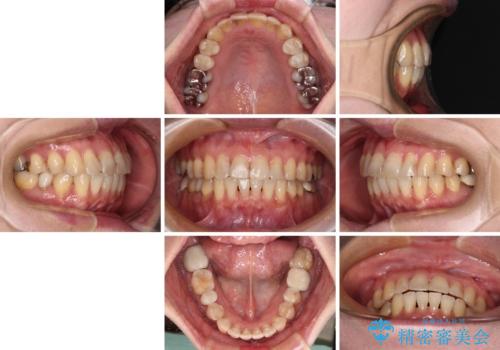

- 前歯のデコボコを気にして来院された患者様です。

インビザラインでもワイヤー装置でも対応可能であったので、両者のデメリットをご説明し、選択していただくことになりました。

マウスピース矯正の装着時間の長さや自己管理の重要性を煩わしいと感じられ、低依存で確実に治療ができるワイヤー矯正を選択されました。

舌突出癖により、上下前歯がなかなか接触せずに治療期間を要しましたが、舌のトレーニングにより無事に治療を終えることができました。